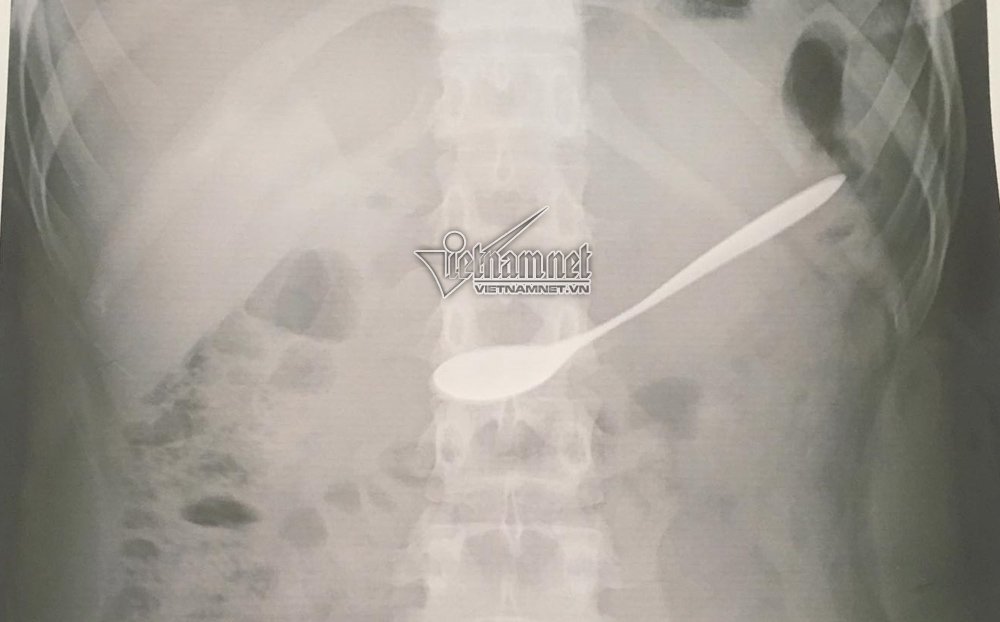

![]() |

| Phim x-quang cho thấy chiếc thìa nằm trong dạ dày |

Tại đây, các bác sĩ đã chụp X-quang, xác định chiếc thìa nằm tại hang vị dạ bày của bệnh nhân.